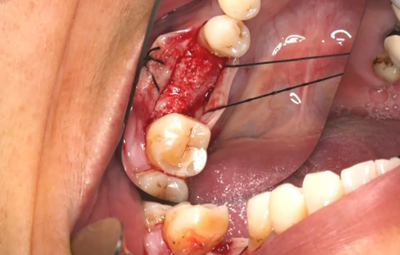

6、牙槽嵴保存術(shù)過(guò)程:拔牙及位點(diǎn)保存

(攝于2016年8月31日)

11、常規(guī)植入WEGO種植體一顆

牙槽嵴頂水平切口,翻瓣,牙槽嵴近中較遠(yuǎn)中豐滿(mǎn)。

(攝于2017年4月14日)